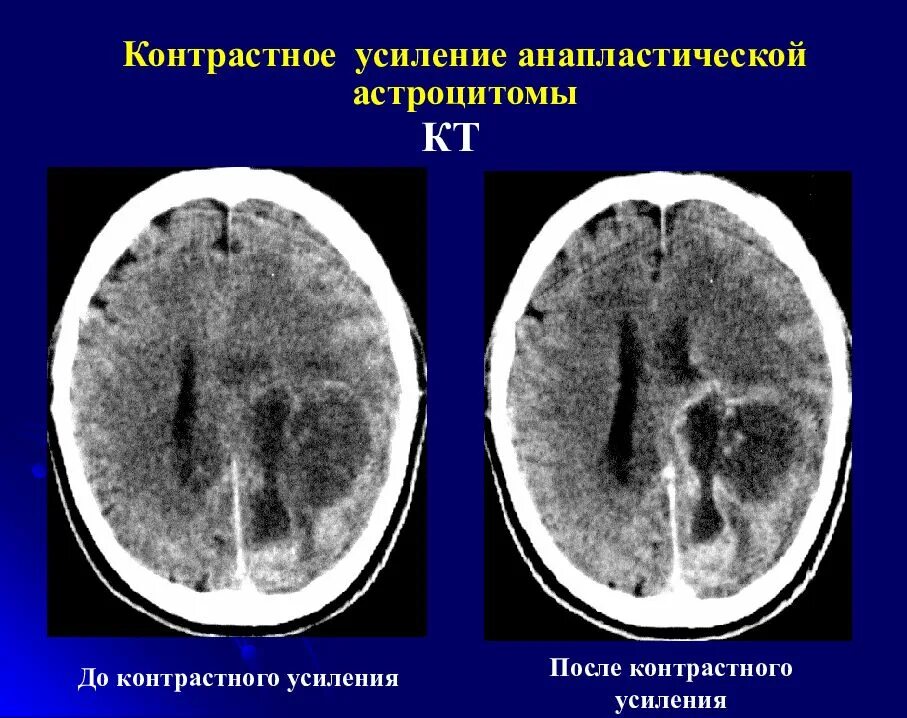

Кт пример